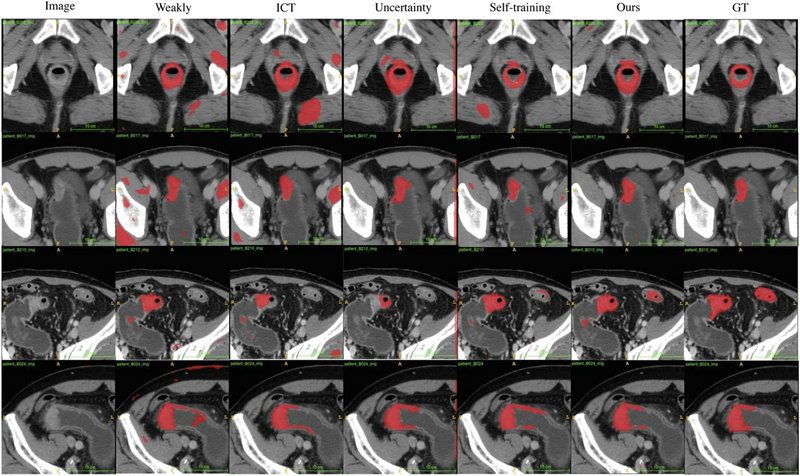

團隊利用來自中山大學附屬第六醫(yī)院和喀地一院的923例有標注結(jié)腸癌CT影像和2670例無標注結(jié)腸癌CT影像作為SOUSA框架的訓練數(shù)據(jù)集,并利用417例結(jié)腸癌CT影像對SOUSA框架進行驗證,結(jié)果顯示其自動分割效果優(yōu)于現(xiàn)有的弱監(jiān)督和半監(jiān)督學習模型。與目前最先進的方法ICT (Verma et al.,2019)、不確定性感知(Yu et al.,2019)和自我訓練相比,SOUSA框架在每個數(shù)據(jù)比率上都達到了最佳性能。此外,當數(shù)據(jù)集的大小有限時,SOUSA框架的性能甚至與使用密集注釋的模型的性能相當。

對腸癌數(shù)據(jù)集使用不同方法的自動分割結(jié)果